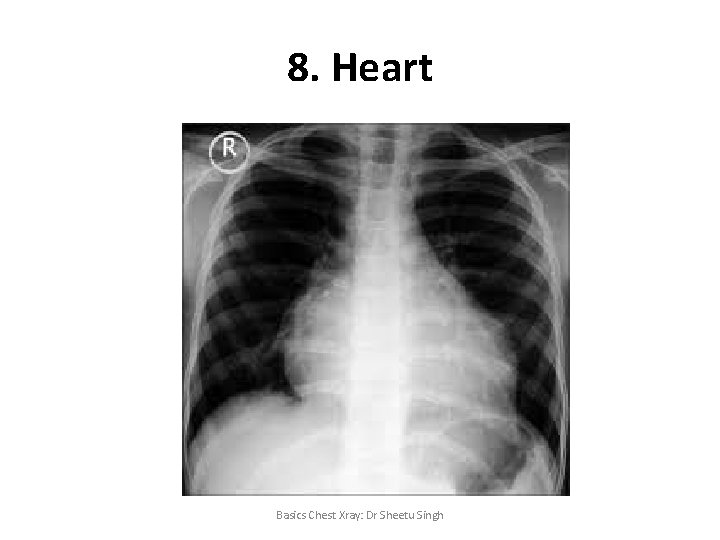

8. Heart Basics Chest Xray: Dr Sheetu Singh